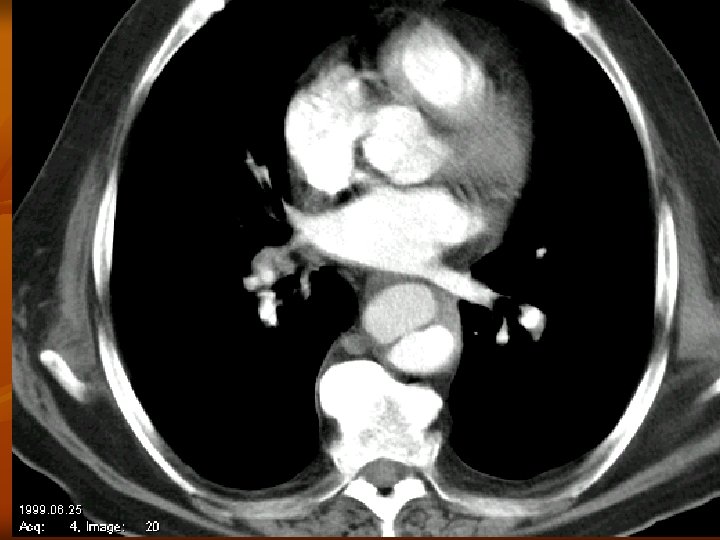

A CTA leggyakoribb alkalmazása dissectio esetén a CTA pontos választ ad: - dissectio fennáll vagy nem a dissectio kiterjedése, típusa kettős lumen megléte pericardium érintettsége supraaorticus ágak érintettsége visceralis ágak érintettsége ruptura occlusio esetén a CTA pontos választ ad az elzáródás helyére, collateralis keringés kialakulására, a parenchyma károsodására